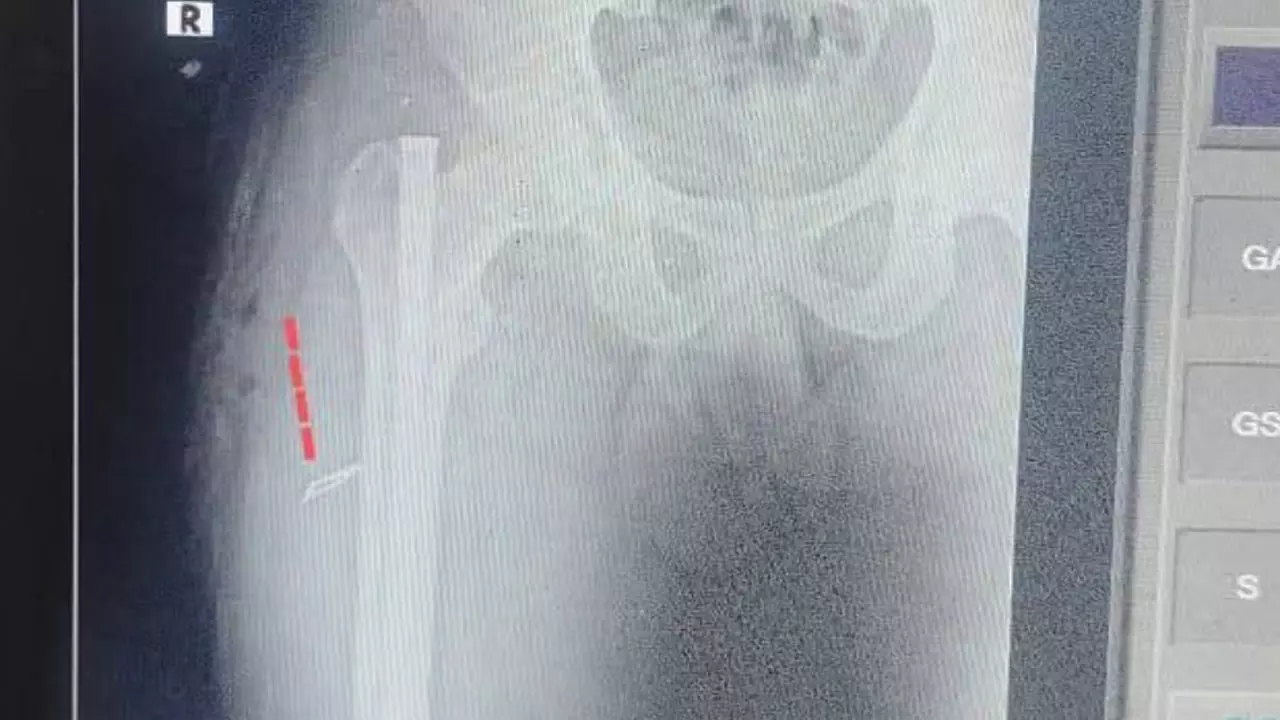

ఎక్స్ రే ద్వారా తేలింది :

అయితే తన కడుపులో బ్లేడ్ ఉన్నట్లుగా ఎక్స్ రేలో తేలింది. దీంతో ఈ వార్త వెలుగు చూడడంతో విధుల నిర్వహణలో బాధ్యతారాహిత్యంగా వ్యవహరించిన వైద్య సిబ్బంది నిర్లక్ష్యంపై మంత్రి సత్యకుమార్ యాదవ్ తీవ్ర ఆగ్రహం వ్యక్తం చేశారు. ఈ ఘటన మీద విచారణ జరిపి నివేదించాలని డైరెక్టర్ ఆఫ్ సెకండరీ హెల్త్ విభాగాన్ని ఆదేశించారు. ఈ మేరకు అయన విచారణ జరిపించారు. తద్వారా వైద్యుడు స్టాఫ్ నర్సు శస్త్రచికిత్స సమయంలో బాధ్యతారాహిత్యంగా వ్యవహరించినట్లు తేలింది అని నివేదిక వచ్చింది. ఈ క్రమంలో వారి మీద సస్పెన్షన్ వేటు పడింది.